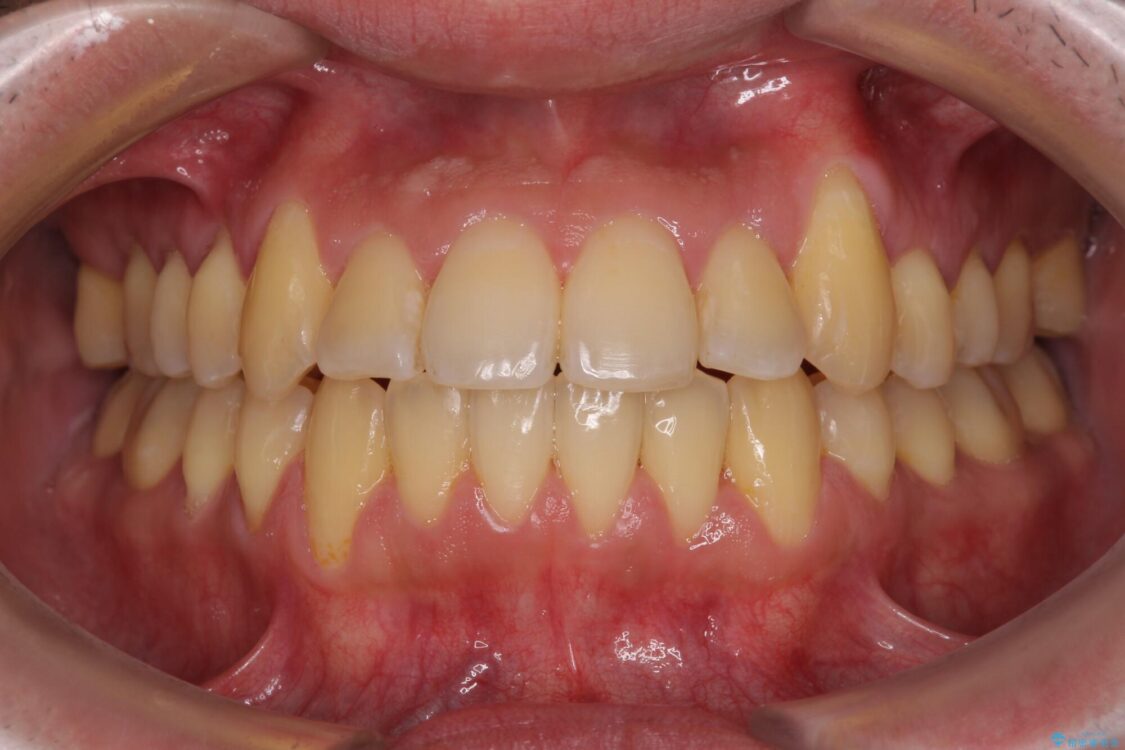

治療後

• 八重歯とクロスバイト 目立たないワイヤー装置で矯正治療 治療後画像